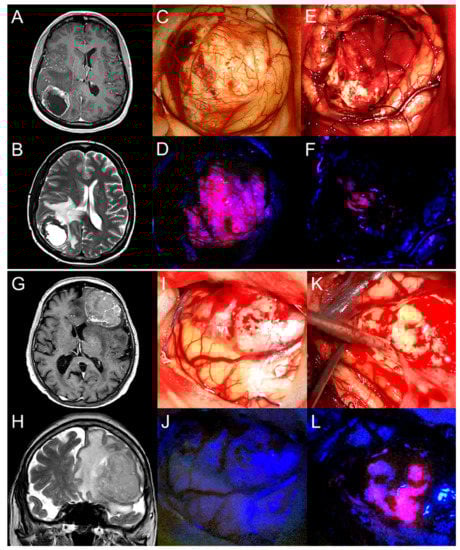

2.2. 5-ALA Fluorescence Characteristics of BM

2.3. 5-ALA Fluorescence Characteristics of Peritumoral Brain Tissue